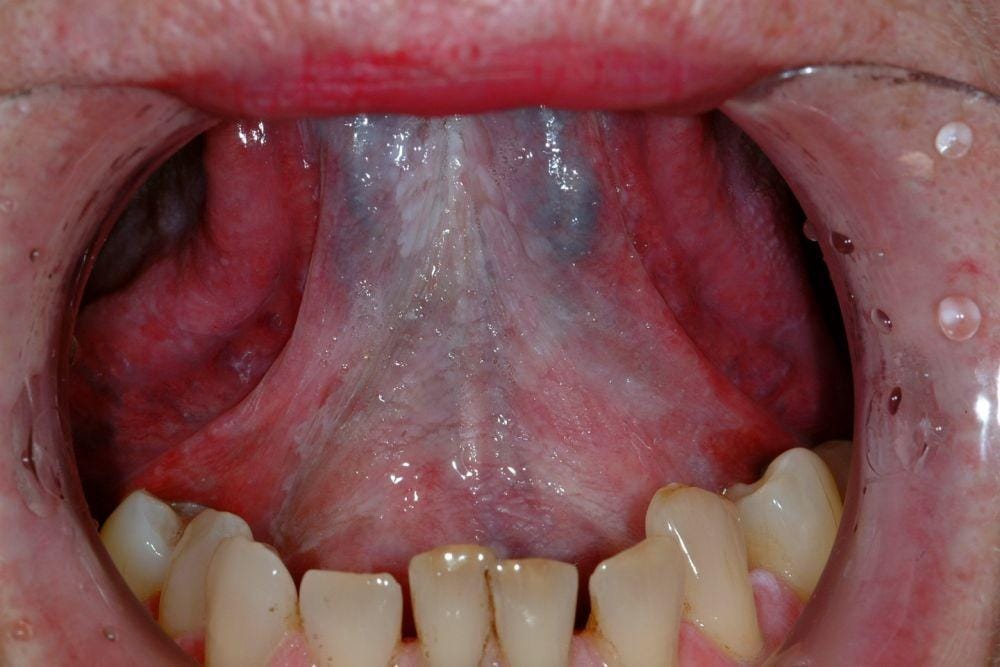

2. Lidah hijau disebabkan oleh infeksi jamur di mulut

Jamur di mulut atau oral thrush adalah tumbuhnya jamur Candida albicans yang berlebihan di mulut sehingga terjadi infeksi. Infeksi ini akan membuat lidah berwarna putih. Namun, lama-kelamaan akan menjadi hijau seiring berjalannya waktu. Selain infeksi jamur, biasanya akan ada benjolan putih di lidah atau amandel dan terasa sakit atau berdarah saat tergores.

3. Lidah berbulu akibat sel keratin, protein yang membentuk rambut dan kuku manusia

Lidah berbulu ini jadi tempat favorit untuk jamur dan bakteri berkembang biak sehingga muncul warna hijau pada lidah. Selain itu, kamu akan merasa lidahmu terbakar, sensasi tak normal, dan bau mulut.

4. Munculnya pola atau lidah geografis

Pola tak teratur di lidah ini seperti kumpulan peta. Itu sebabnya disebut lidah geografis. Pola ini berwarna merah gelap di tengah dan keputihan di tepiannya. Lama-kelamaan, lidah akan berubah warna jadi hijau. Kadang, gejala ini disertai rasa tak nyaman dan sensasi terbakar, setelah makan makanan asam atau pedas.

5. Mengalami lichen planus akibat perkembangan bakteri dan jamur

Gejala ini juga bisa disebabkan oleh konsumsi makanan, minuman, dan produk tertentu. Adapun, kamu akan melihat adanya luka putih di mulut dengan sensasi terbakar.

6. Kanker mulut dengan munculnya luka yang tak kunjung sembuh di lidah

Kanker mulut ini biasanya diikuti dengan tumbuhnya bakteri atau jamur serta makan makanan tertentu. Kanker mulut ini biasanya disertai dengan gusi berdarah, kesemutan, penurunan berat badan, sakit tenggorokan, dan muncul luka di lidah.